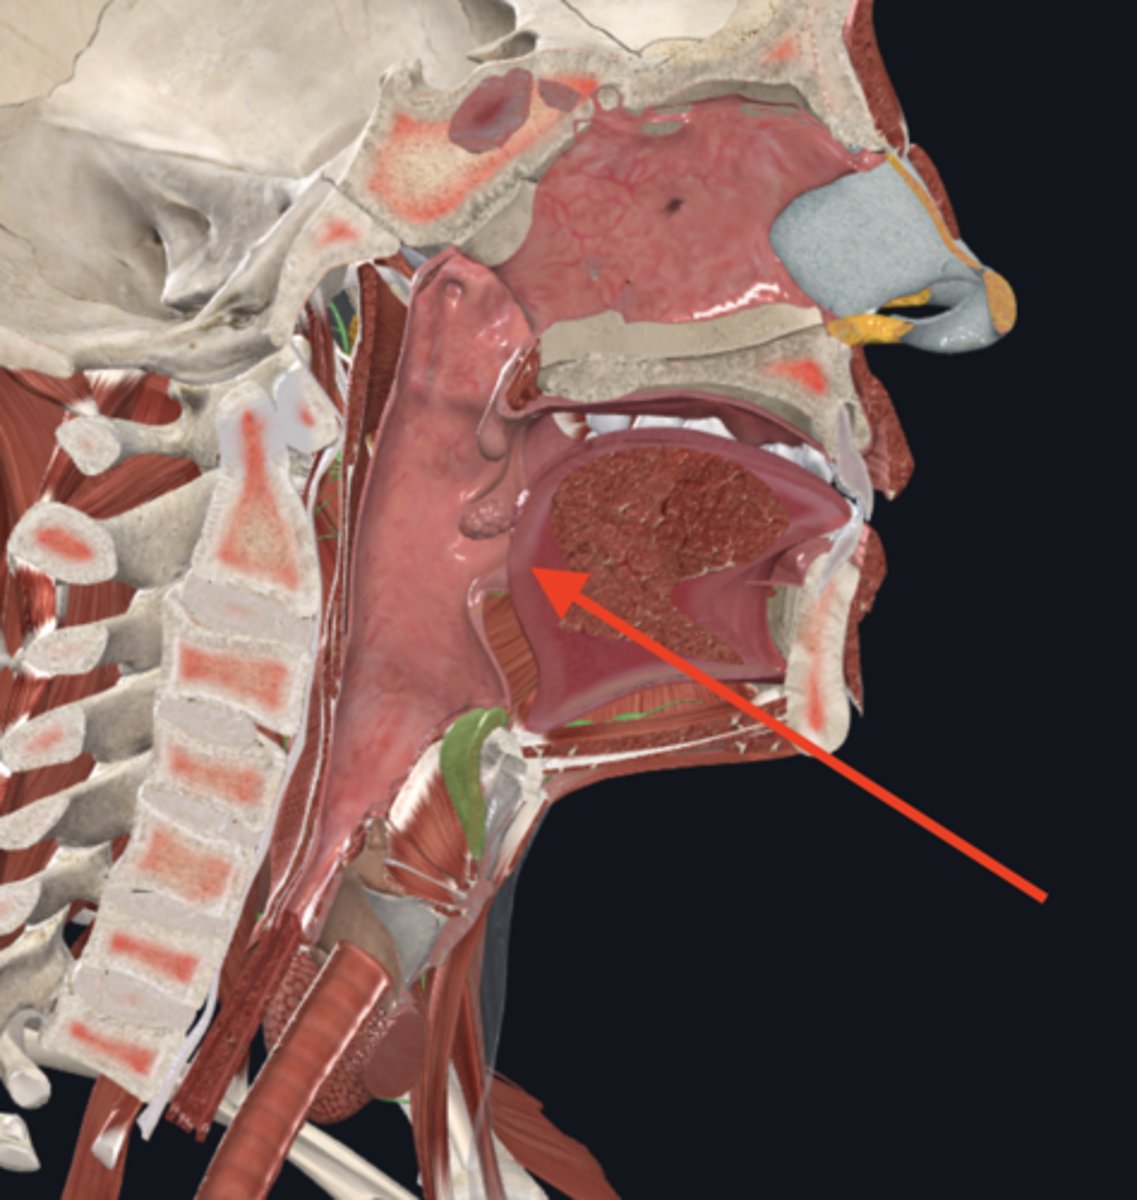

nasopharynx

name the circled region

oropharynx

name the circled region

laryngopharynx

name the circled region